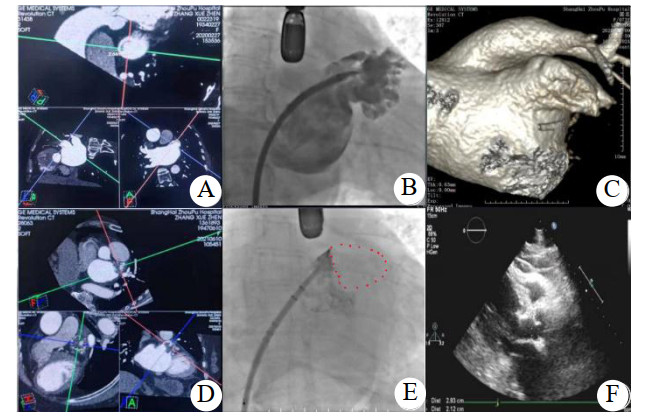

本组病例LAAC后心脏压塞发生率,Watchman为0.71%(4/562例),LAmbre为0.93%(2/216例),LACbes为6.6%(6/91例),Laager为6.25%(1/16例);同期文献报道LAmbre心脏压塞发生率2.2%(5/224例)[9]。平均左心房直径(43.2± 5.3)mm,6例LAAC联合冷冻消融手术;左心耳菜花型8例,鸡翅型5例;左心耳/ 肺动脉位置B型11例,A型1例(病例13),C型1例(病例8);B型患者D10为(2.15± 1.5)mm,D15为(1.71± 1.5)mm,minD_深度(10± 2.6)mm;盘式封堵器密封盘平均直径(29.5± 2.8)mm;心脏压塞恢复后复查CTA患者10例,封堵器展开完全,8例锚钩贴靠肺动脉,病例8为鸡翅型左心耳,左心耳肺动脉位置C型,封堵器锚钩贴靠左上肺静脉;病例13为鸡翅型左心耳,左心耳肺动脉位置A型,封堵器锚钩贴靠左上肺静脉,见表 2。本研究汇总同期LAAC后左心房CTA复查病例,封堵器锚钩贴近肺动脉及左上肺静脉发生率为20%。代表性LAAC病例2,12,见图 1和图 2。

| 患者(病例2)心脏CTA检查(A:左心耳近中段与肺动脉主干近段毗邻密切,C:左心耳菜花型,D:左心耳置入33 mm Watchman后,封堵伞包括锚钩处贴靠肺动脉);DSA(B:左心耳造影为菜花型,E:左心耳置入Watchman未见封堵伞周围漏);4个月后心脏压塞发生时床边超声心动图(F:中-大量心包积液,左室后壁21.2 mm) 图 1 左心耳置入Watchman封堵器后4个月发生延迟性心脏压塞 Fig 1 Delayed cardiac tamponade occurred 4 months after LAAC with Watchman |